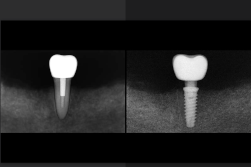

Autrefois, la fameuse dent sur pivot était la solution de référence pour sauver une dent très abîmée.